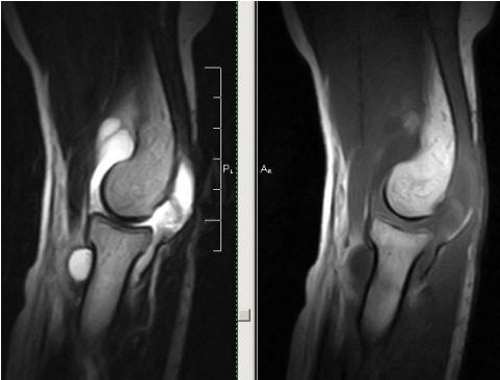

Неспецифический серозный синовит локтевого сустава проявляется увеличением сустава из-за накопления жидкости. Контуры сустава становятся менее четкими, что заметно даже на фотографиях. Пациенты ощущают распирание, а боль имеет тупой и неярко выраженный характер. Функции сустава нарушаются, объем движений уменьшается. При осмотре выявляется положительный симптом флюктуации, указывающий на наличие жидкости. Кожа над пораженным локтем отечная, гиперемированная, местная температура повышена. В редких случаях могут наблюдаться симптомы общей интоксикации: слабость, потливость, субфебрильная температура.

Острый гнойный синовит локтевого сустава характеризуется интенсивной болью, из-за которой пациент избегает любых движений рукой. Сустав отекает, кожа гиперемирована, иногда развивается контрактура. Наблюдаются все признаки острого воспалительного процесса: повышенная температура тела, озноб, резкая слабость и увеличение близлежащих лимфатических узлов.

Хронический локтевой синовит может быть серозным, серозно-фибринозным или вилезно-геморрагическим. Клинические проявления выражены слабо: наблюдается незначительная боль в суставе, рука быстро утомляется, особенно при выполнении однообразных движений.